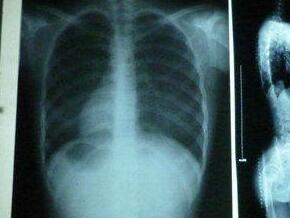

(图:李先生2018年拍的X光片)